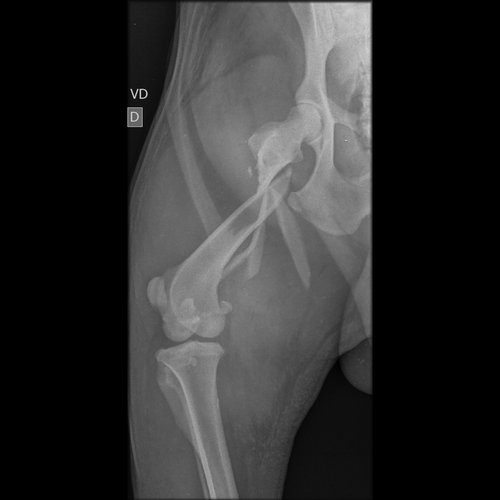

Oi, eu sou a Maria Eduarda, estudante de medicina veterinária e hoje chegou na clínica que eu estou estagiando, um cachorro de rua atropelado, com fratura em femur e tibia e doença do carrapato.